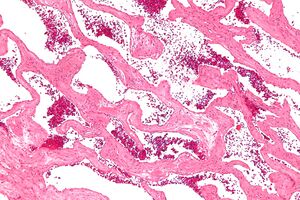

| Micrograph of a cavernous liver hemangioma. H&E stain. | |